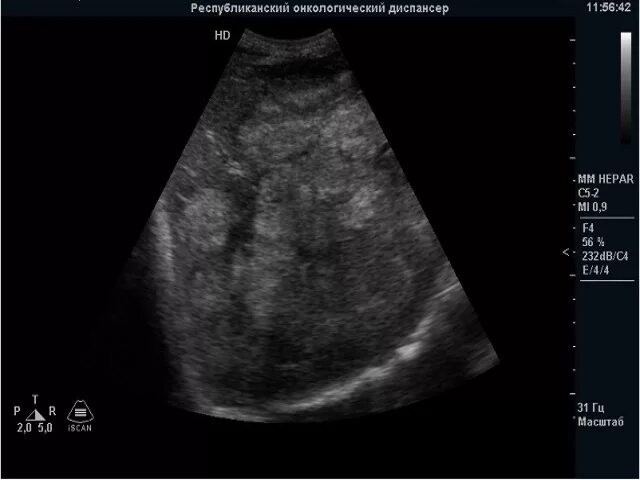

Метастазы в печени на узи